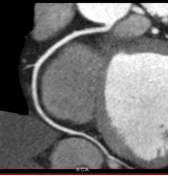

This latest 64 slice CT machine has a special role in Cardiac Angiography, since this investigation has been found to be a viable alternative to catheter angiography. Cardiac coronary Angiography has been found to be highly sensitive and specific in diagnosing coronary artery stenosis, stenosis in coronary stents and occluded coronary bypass grafts. The added advantage of Cardiac CT angiography is that it is completely non invasive, unlike catheter angiography. Also it is the modality to detect and characterize silent non-obstructive atherosclerotic plaques, which may be associated with adverse outcome and cannot be picked up on catheter angiography

Normal RCA